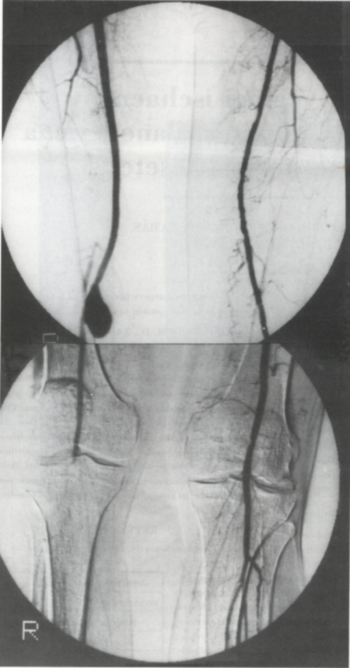

Az elvégzett pelveo-femoralis angiográfia a korábbi bypass alsó anasztomózisának megfelelően 1,5 x 2,5 cm-es álaneurysmát mutatott a kiáramlási pálya teljes hiányával (1. ábra).

1. ábra.

A pelveo-femoralis angiográfia 1,5 x 2,5 cm-es álaneurysmát mutatott, a kiáramlási pálya teljes hiányával.

Az elvégzett kontroll angiográfia mutatja a jól vezető interpositumot, valamint a rekanalizált kiáramlási pályát (2. ábra).

2. ábra.

A kontroll angiográfia mutatja a jól vezető interpositumot és a rekanalizált kiáramlási pályát.